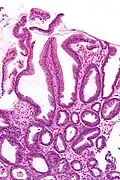

| Micrograph of a reactive gastropathy. H&E stain. | |

- Foveolar hyperplasia (black arrow), as a tortuosity in the "neck" region of the gastric glands.

- Scant or minimal inflammatory cells (white arrow), i.e. lack of large numbers of neutrophils and plasma cells..

- Smooth muscle hyperplasia in the lamina propria (in black oval).

The diagnosis is by examination of tissue, e.g. a stomach biopsy.

High mag.